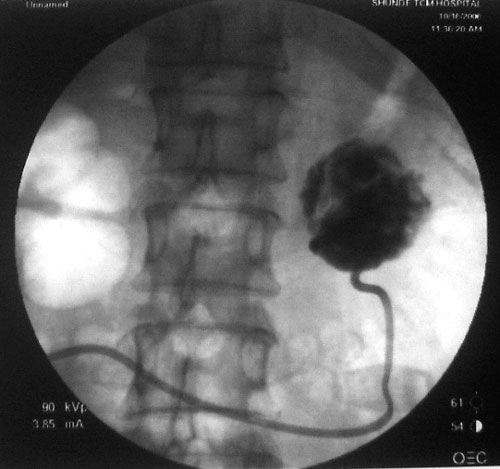

参照ct片,经皮穿刺,抽出透明液体60ml,随后置入引流管引流,囊液细胞学检查阴性,胰酶检查阴性。采用无水乙醇灌注治疗。4天后囊腔闭锁,无液体渗出,予以拔管。

置管后造影,显示囊腔直径约5cm,囊壁光整,正位、双斜位造影均未见造影剂外溢,与胰腺无交通